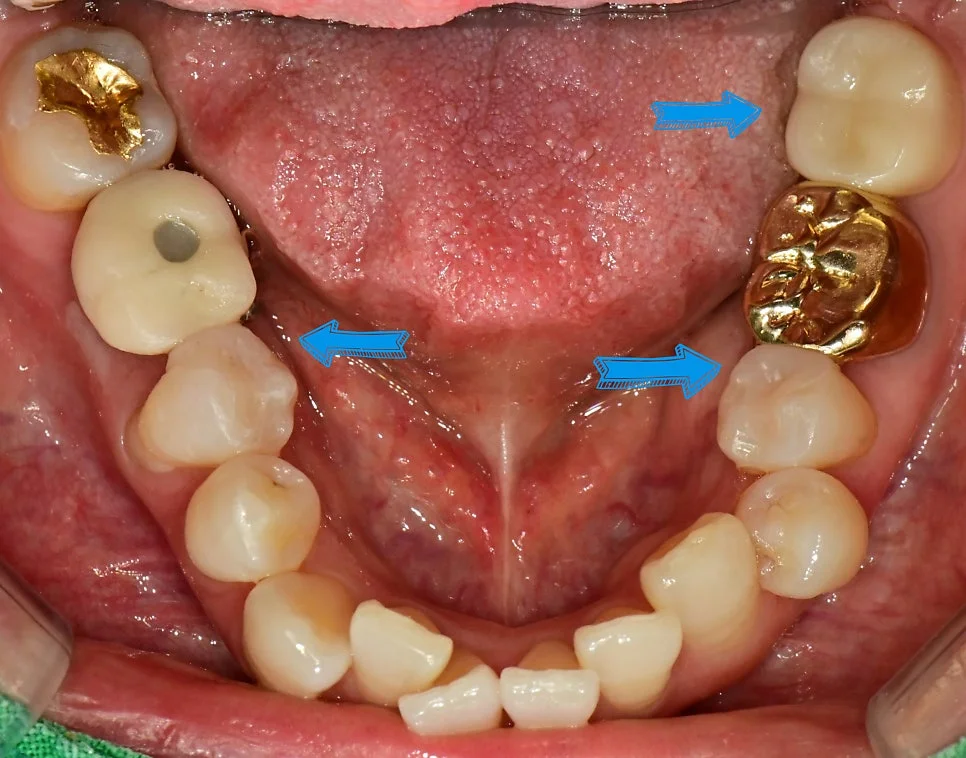

충치 검사와 스케일링을 원해 내원하셨습니다.

환자 초진 구강 사진 — 전체적인 치아 상태 확인

오른쪽 아래의 충치 진단

오른쪽 아래를 살펴보니 임플란트와 바로 앞 치아 사이에 벌어진 틈이 보입니다!

이렇게 틈이 벌어지면 음식물이 많이 끼게 되고 그 과정에서 충치가 생기는 경우가 흔한데요. 교익 방사선(Bitewing X-ray) 사진 촬영을 통해 치아 사이 충치를 확인해 보았는데요!